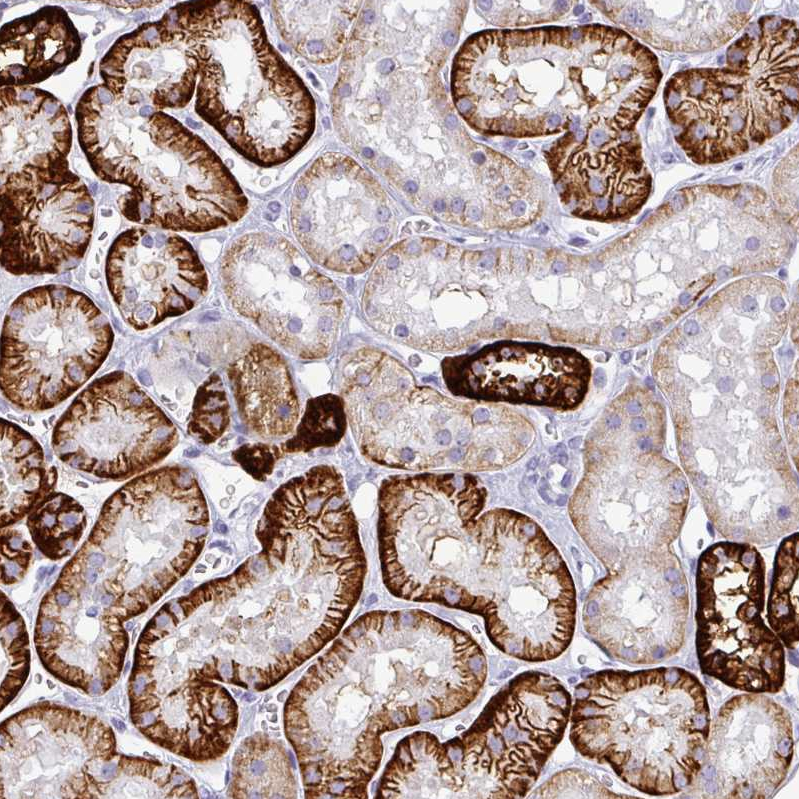

Immunohistochemistry analysis in human kidney and testis tissues using HPA036260 antibody. Corresponding CDH16 RNA-seq data are presented for the same tissues.